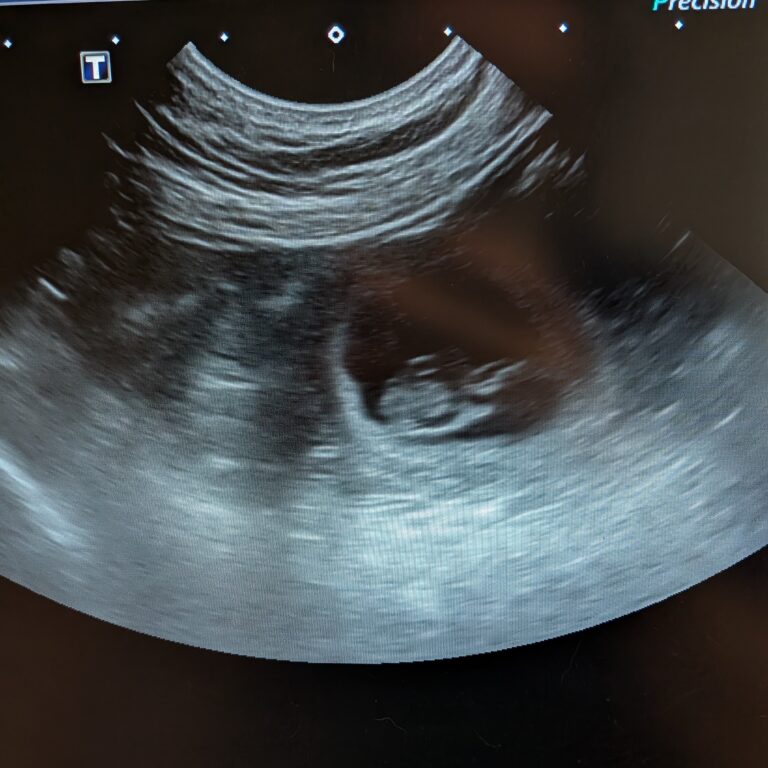

Dans chaque regard de Golden, il y a une leçon d’amour inconditionnel!